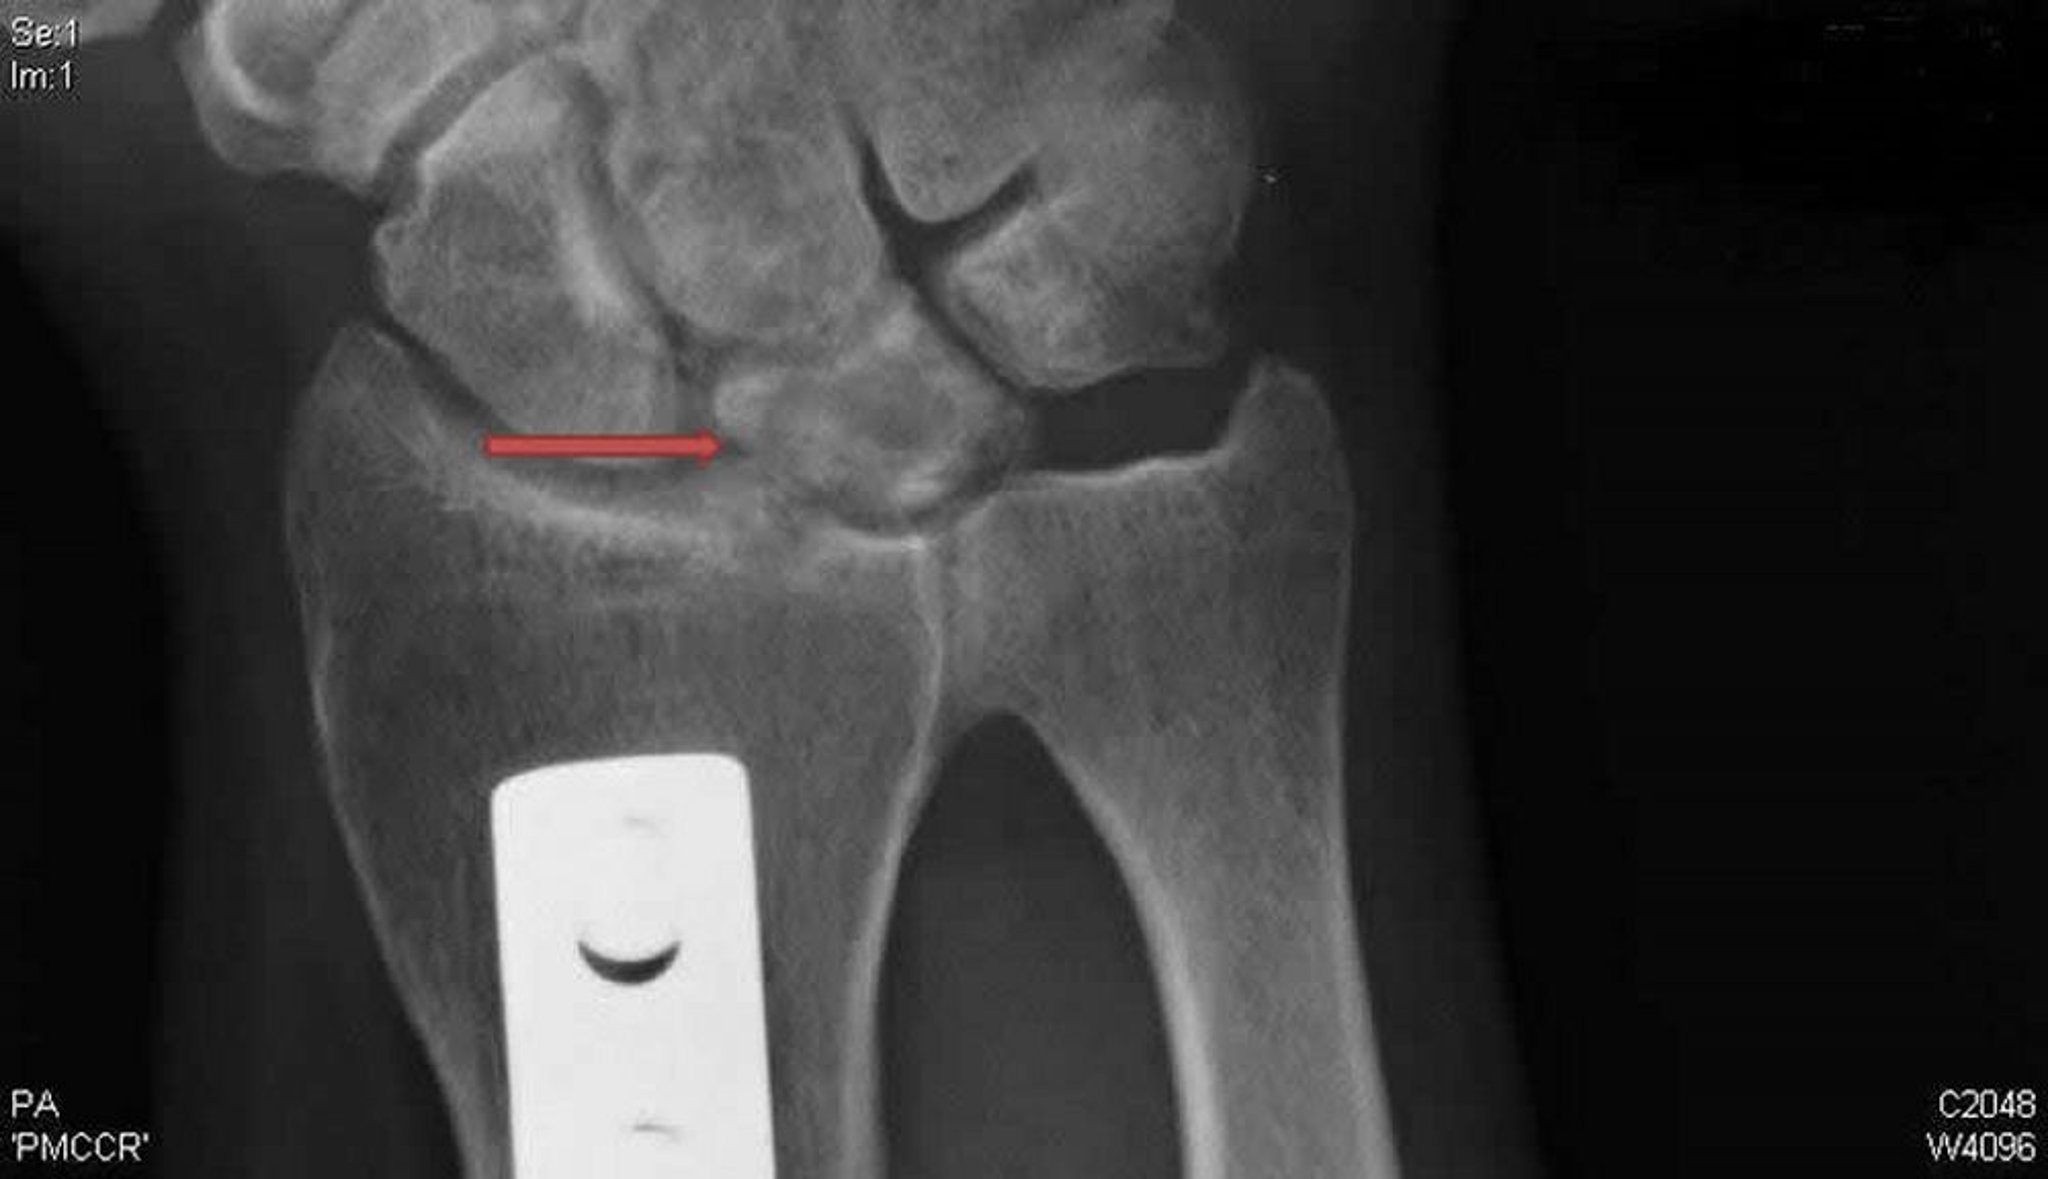

Хвороба Кінбека (рентгенограма у передньо-задній проекції)

This posteroanterior radiograph of the right wrist shows cysts and sclerosis of the lunate bone (arrow) typical of Kienböck disease. The metal plate is evidence of a radial shortening osteotomy that was done in an effort to unload the lunate and potentially treat this condition.

Radiograph courtesy of David R. Steinberg, MD.